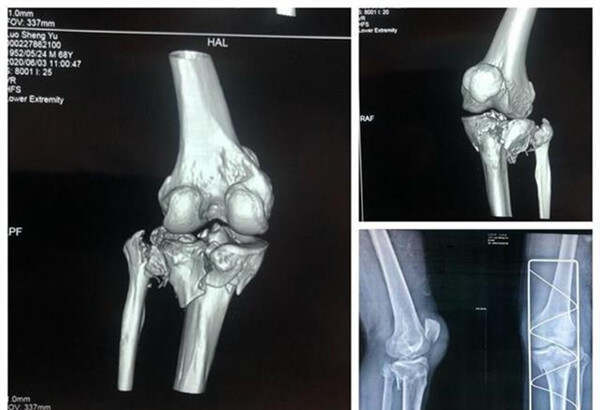

今年68歲的羅爹爹,因車(chē)禍導(dǎo)致頭部、左膝部受傷,入院診斷:硬膜外血腫、左脛骨平臺(tái)粉碎性骨折(SchatzkerⅥ型)、左腓骨小頭骨折??紤]該患者年齡大,合并腦部損傷,骨折粉碎嚴(yán)重,為縮短手術(shù)時(shí)間、提高效率和手術(shù)質(zhì)量,該院骨科主任楊俊忠提出了用3D打印技術(shù)輔助手術(shù)治療,制定手術(shù)方案,精準(zhǔn)治療。

數(shù)字化設(shè)計(jì)結(jié)合3D打印技術(shù),打印出了受損的脛骨、腓骨、股骨模型。在楊俊忠?guī)ьI(lǐng)下骨科創(chuàng)傷關(guān)節(jié)專(zhuān)家組成員副主任醫(yī)師胡浩、副主任熊家亭、醫(yī)師黃攀、黃傳文進(jìn)行了術(shù)前的討論,根據(jù)模型精準(zhǔn)了解骨折類(lèi)型,設(shè)計(jì)手術(shù)切口、預(yù)演術(shù)中步驟、內(nèi)植物的安放位置及術(shù)中復(fù)位技巧,制定出可行的治療方案,手術(shù)按照計(jì)劃進(jìn)行,術(shù)后的康復(fù)也令人滿(mǎn)意。